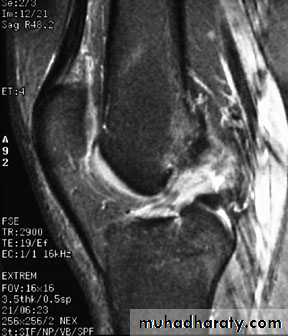

2.MRI

.Meniscal & ligamentous tears in the knee .

Usually caused by staphylococcus aureus , there is rapid destruction of the articular cartilage followed by desdtruction of the subchondral bone and soft tissue swelling seen around joint . Joint effusion is first sing which can be detected by U/S , MRI is often performed if diagnosis is still in doubt.Tuberculous arthritis: